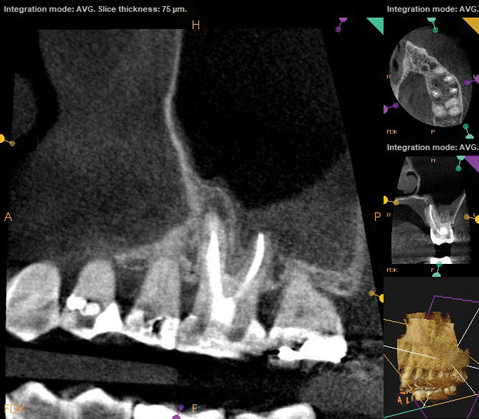

As part of the endodontic evaluation, CBCT imaging showed periapical pathology associated with tooth No. 14 as well as significant MSEO (Figure 7 and Figure 8). Clinical testing confirmed the absence of a cold response but no tenderness to percussion or palpation. A composite buildup was in place, absent evidence of recurrent decay. Soft tissues were unremarkable.

Fig 7 and Fig 8. Preoperative CBCT scans showing evidence of periapical pathology on tooth No. 14 as well as communication with the adjacent maxillary sinus and associated mucositis. Fig 7: Sagittal view, buccal roots No. 14. Fig 8: Sagittal view, palatal root No. 14.

Fig 8. Preoperative CBCT scans showing evidence of periapical pathology on tooth No. 14 as well as communication with the adjacent maxillary sinus and associated mucositis. Fig 7: Sagittal view, buccal roots No. 14. Fig 8: Sagittal view, palatal root No. 14.